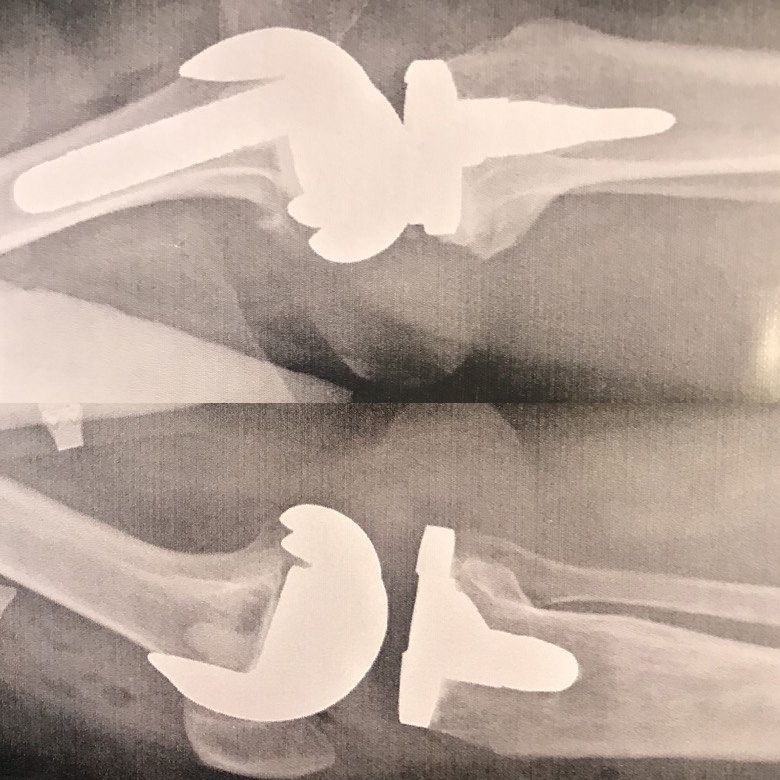

Diz eklemi değişimi

Diz eklemi protezi, hasarlı eklemin yerine yapay bir eklem veya protezin yerleştirildiği bir ameliyat türüdür.